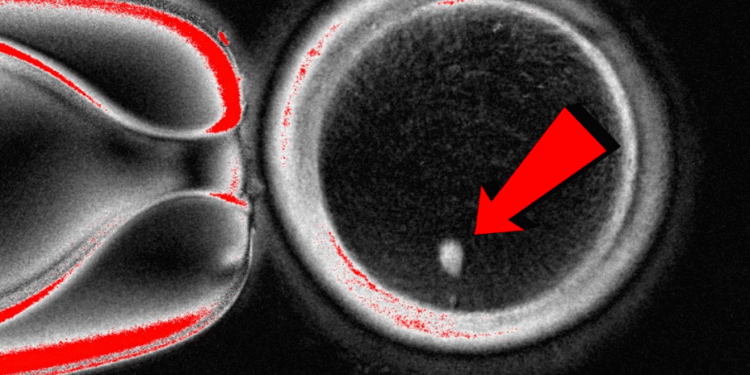

For the first time, researchers say they’ve created human eggs from skin cells—a breakthrough that raises enormous ethical, moral, and biblical concerns.

The technique could open the door for same-sex couples to have children genetically related to both partners, and could also help women unable to produce viable eggs. Lead researcher Shoukhrat Mitalipov explained, “This technology would allow many of these women to have genetically their own eggs and to have a genetically related child.”